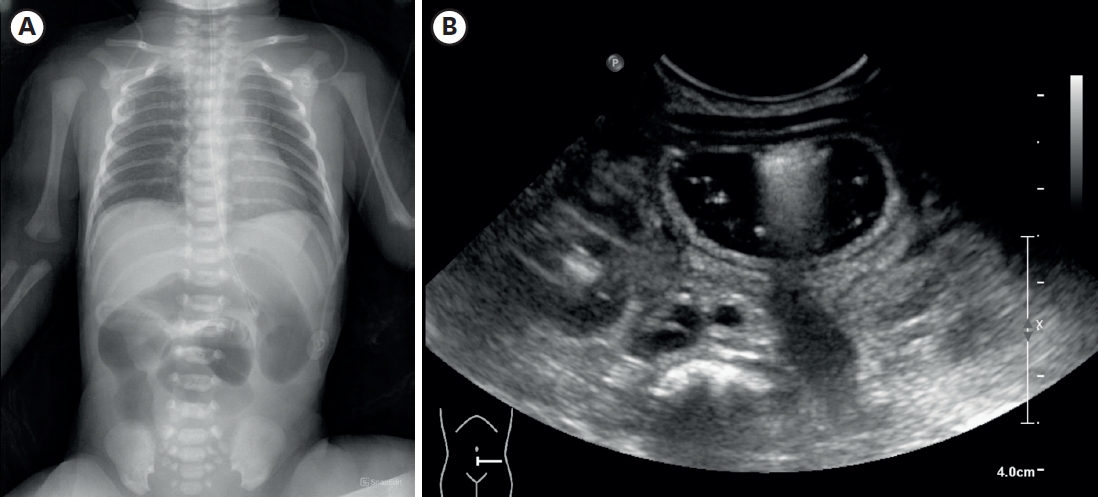

A female infant was born as a twin 1st baby via cesarean section at 35+2 weeks gestation, weighing 2,260 g. Her 38-year-old mother had a history of gestational diabetes, and experienced premature membrane rupture during referral to our hospital. The prenatal ultrasound showed fetal bowel dilatation suggesting small bowel obstruction. Gastric tube drainage was bile-stained, and the abdomen was mildly distended, but not tense. Infantogram showed several distended proximal small bowel loops, with nonvisible rectal gas (Fig. 1A). On the postnatal ultrasound, the rectum and distal sigmoid were all collapsed, with no signs of malrotation or midgut volvulus (Fig. 1B). There was no family history of malformation, and aside from a small atrial septal defect detected on echocardiography, she had no other anomalies.

Fig. 1.

Imaging performed after birth. (A) Infantogram showing multiple dilated loops of small bowel. (B) Following ultrasonography showing dilated proximal small bowel filled with fluid, without definite wall thickening or abnormal vascularity.

Fig. 1. Imaging performed after birth. (A) Infantogram showing multiple dilated loops of small bowel. (B) Following ultrasonography showing dilated proximal small bowel filled with fluid, without definite wall thickening or abnormal vascularity.